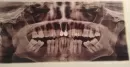

Хочу снять старые металлокерамические коронки с передних двух верхних зубах, а на их место поставить коронки из диоксида циркония.

Если культевая вкладка металлическая (есть ли она вообще на снимке?), то можно ли на нее поставить коронку из диоксида циркония? Не будет ли она просвечиваться? Могу ли я сделать данную операцию? Есть ли на моем снимке то, что, может мне помешать, это сделать?

Вкладка есть, но материал вкладки по снимку не определить. Как правило, при грамотном подходе вкладка через коронку не просвечивает.

Вам необходимо обратиться к стоматологу-ортопеду. Врач в ходе клинического осмотра и оценки прицельного снимка сможет определить состоятельность данной вкладки.